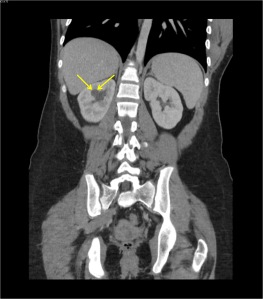

History: 16 year old female with recurrent flank pain.

This is the appearance of a calyceal diverticulum, which is a small outpouching or eventration of a calyx into the renal parenchyma. They are usually connected by a narrow channel to the renal pelvis, as seen in the IVP image above. A calyceal diverticulum can be complicated by renal colic (renal stone), which was the cause of recurrent flank pain in this patient. Occasionally, milk of calcium can precipitate or layer within the calyceal diverticulum and mimic a renal stone. Most commonly, a calyceal diverticulum is incidentally discovered as they are typically asymptomatic.